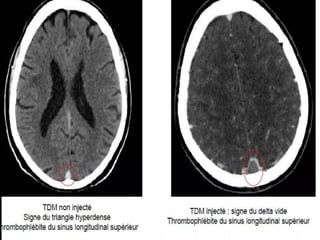

• Occlusion des sinus veineux cérébraux souvent associés à une

• SCANNER et ANGIO SCANNER: Sans /Avec inj:

Sans inj: hyperdensité spontanée du thrombus au sein d’un sinus

veineux=SIGNE DU TRIANGLE DENSE.

• SCANNER avec inj: Zone hypodense d’un sinus(thrombus) cernée

d’une importante prise de contraste de la paroi du sinus réalisant

le SIGNE DU DELTA ou du TRIANGLE VIDE: ++++SIGNE DIRECT

• Occlusion dessinus veineux cérébraux souvent associés à une thrombose des veines corticales • SCANNER et ANGIO SCANNER: Sans /Avec inj: Sans inj: hyperdensité spontanée du thrombus au sein d’un sinus veineux=SIGNE DU TRIANGLE DENSE. • SCANNER avec inj: Zone hypodense d’un sinus(thrombus) cernée d’une importante prise de contraste de la paroi du sinus réalisant le SIGNE DU DELTA ou du TRIANGLE VIDE: ++++SIGNE DIRECT ANGIO IRM(ARM): ARM: Absence de flux